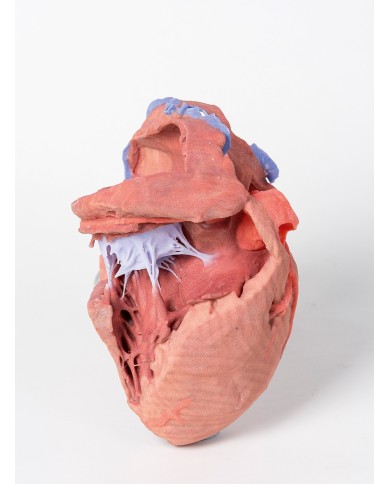

Modello di cuore di alta qualità scomponibile in 5 parti

Modello di cuore di alta qualità scomponibile in 5 parti

La parete anteriore del cuore è staccabile per poter vedere i ventricoli.

Realizzato in stampa 3D ad elevatissima risoluzione a colori.